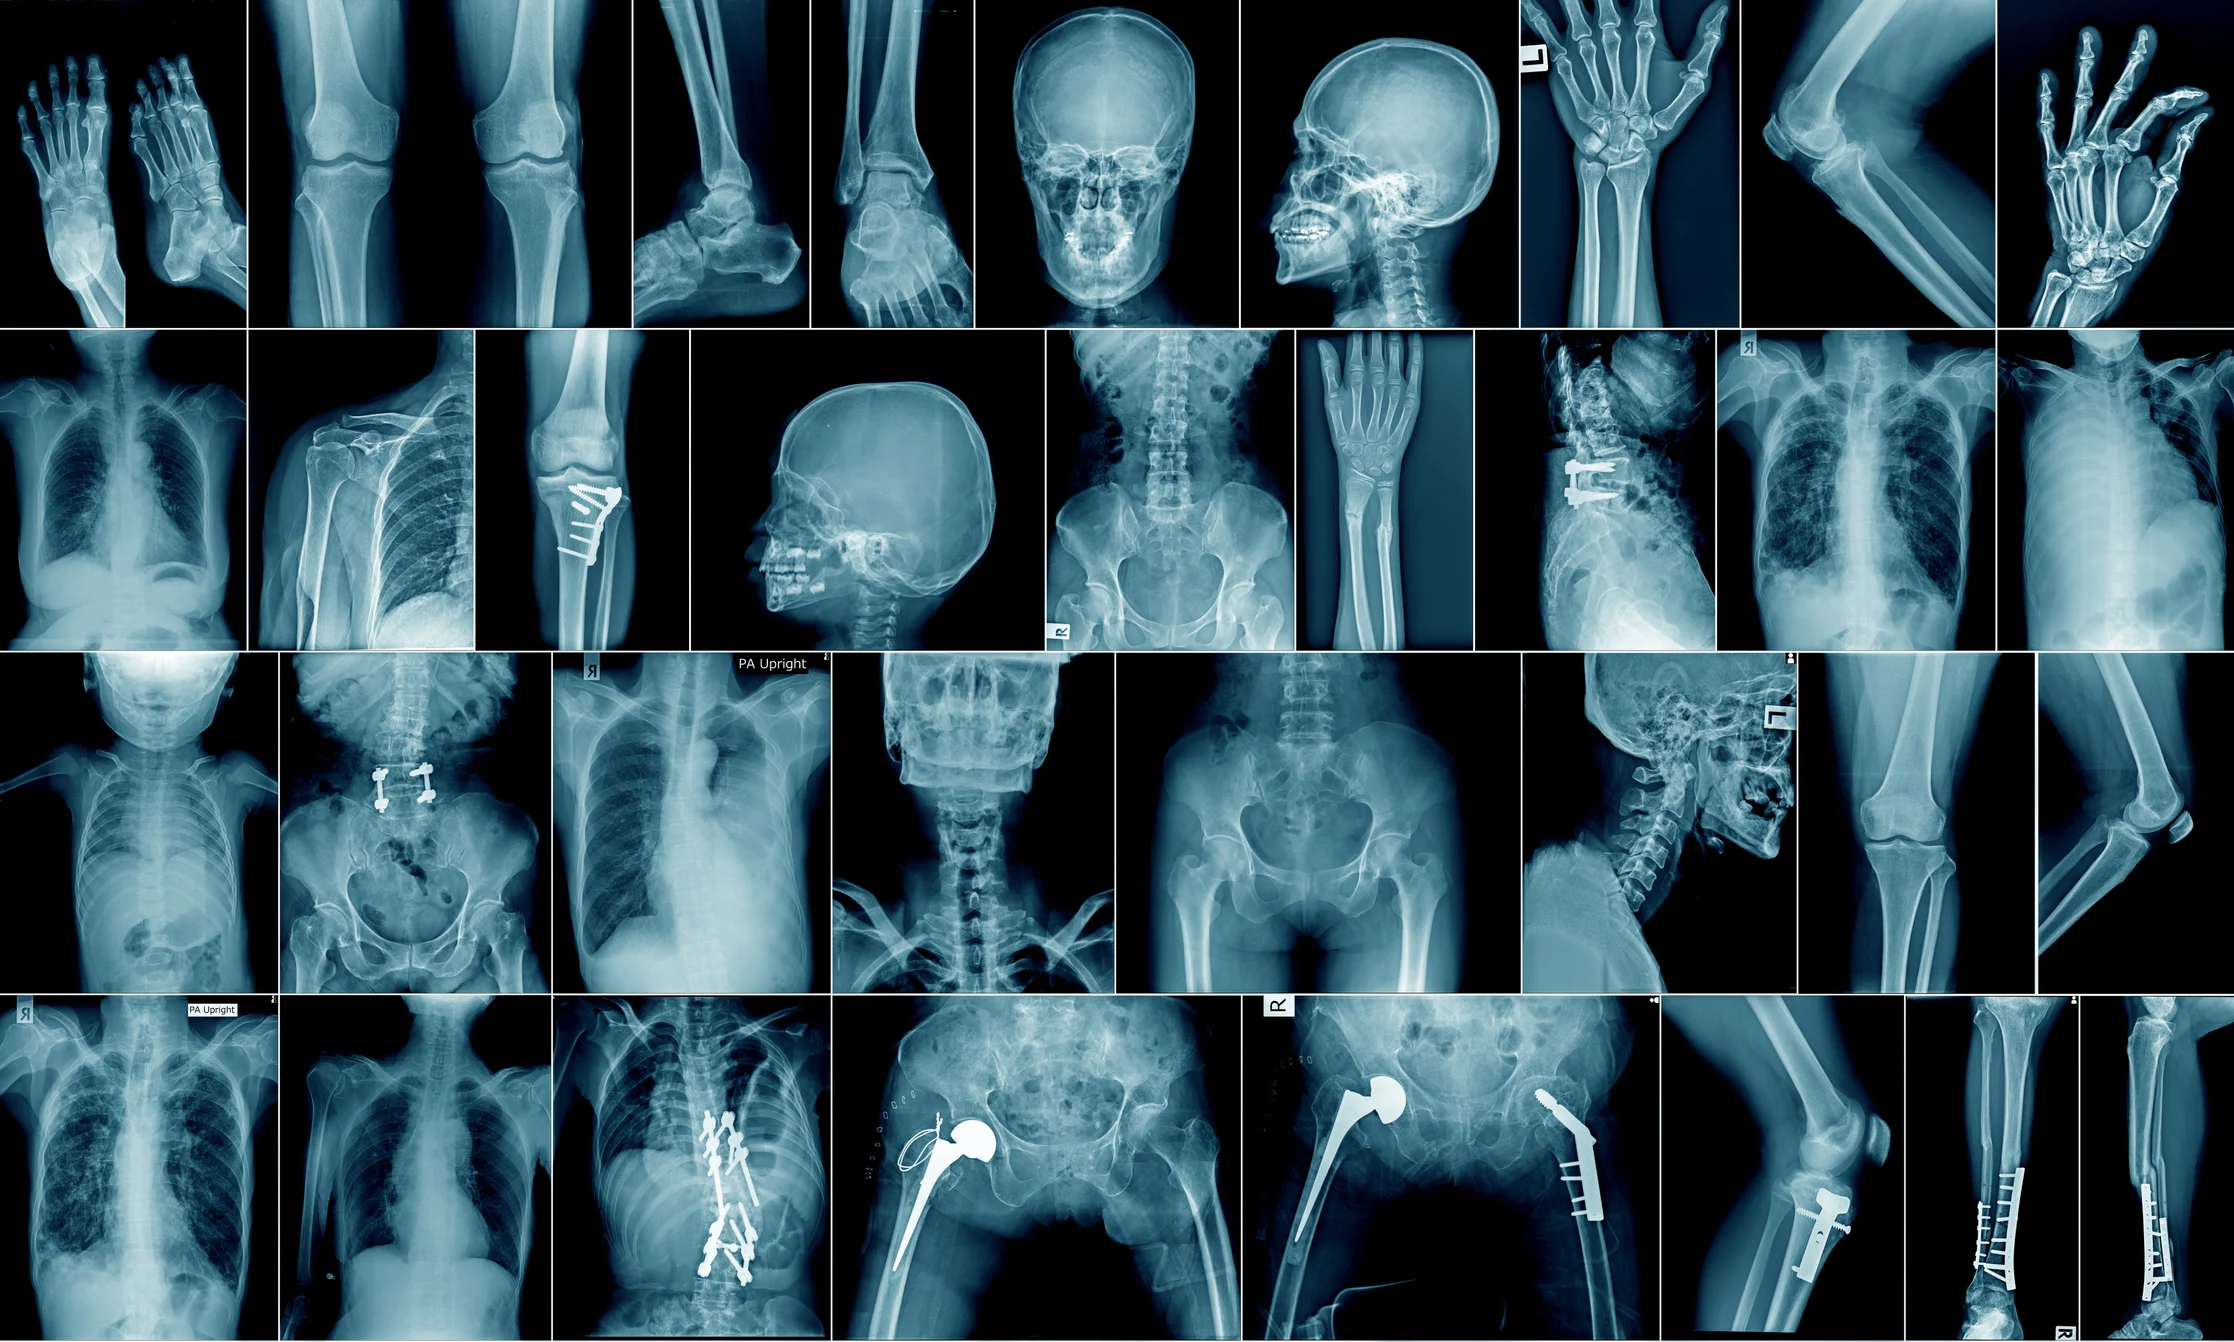

Impacto dos microplásticos nos ossos humanos

Pesquisas recentes sugerem que o contato constante com microplásticos pode prejudicar as células-tronco da medula óssea, interferindo na formação de osteoclastos, células responsáveis pela degradação do tecido ósseo.

Esse processo, conhecido como reabsorção óssea, pode promover inflamações crônicas e enfraquecimento dos ossos, aumentando o risco de fraturas.